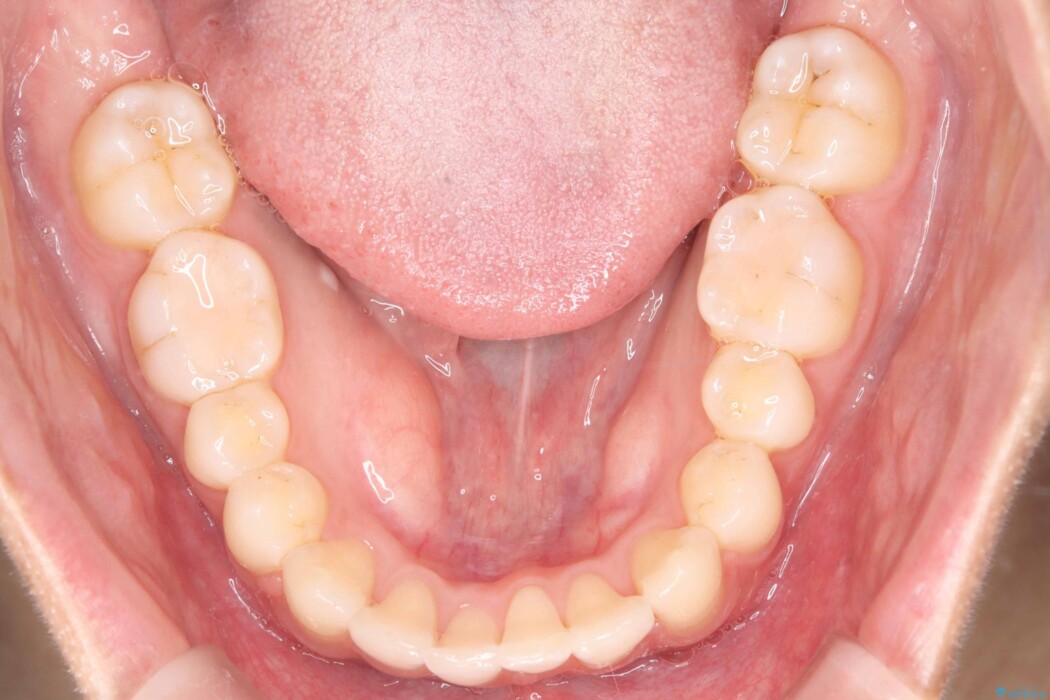

歯の移動量や力のコントロールを最適化することで、短期間で治療完了しました。

「矯正は時間がかかる」というイメージをお持ちの方も多いですが、症例によっては、非抜歯でも短期間で改善が可能な場合があります。

治療後は歯並び・かみ合わせともに大きく改善し、患者様にも大変ご満足いただけました。